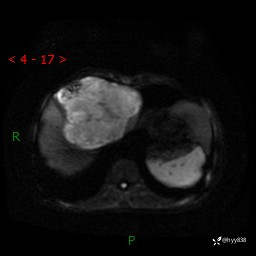

【患者信息】:58岁/男

【主诉】:发现肝占位2天

【现病史及既往史】:患者2天前于当地市第五医院查上腹部磁共振提示:肝脏S4段占位性病变,肝ca可能,胆囊结石,腹膜后多发肿大淋巴结,无剑突下及右上腹疼痛不适,无明显反酸、嗳气,无畏寒、头晕、头痛,无尿频、尿急、尿痛等不适,今为求进一步治疗特来我院就诊,门诊以“肝占位”收住我科。 患者病程中精神、睡眠、饮食尚可,大小便正常、体力体重无明显变化

【检查】:肝脏MRI】平扫+增强